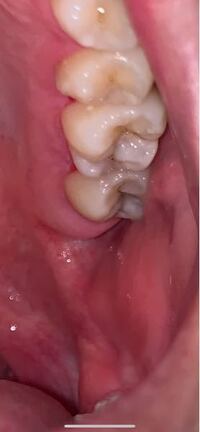

虫歯についてです 汚い写真で申し訳ないですが 奥歯がこのように灰色 Yahoo 知恵袋

これは虫歯でしょうか? 奥歯の噛む部分の一部が、 白ではなく、薄い灰色になっています。 はっきりと黒いわけではなく、絵の具の灰色に白を混ぜたようなぼんやりとした色です。 ただ4~5年ほど前治療方法 虫歯を削って、詰め物をする 保険治療コンポジットレジン修復(詰め物) 虫歯部分を削り、白いプラスチック(レジン:合成樹脂)の詰め物を詰めます。